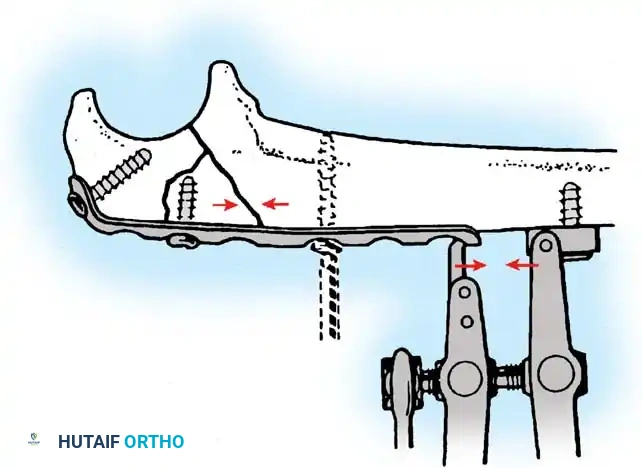

If comminution with bone loss prevents the use of a tension band compression technique—due to the risk of shortening the olecranon and narrowing the greater sigmoid notch—plate fixation is mandatory. Plating is also the gold standard for Monteggia fracture-dislocations, oblique fractures extending distally, and fractures involving the coronoid process.

Hand-contoured reconstruction plates or modern, anatomically precontoured locking plates (e.g., Acumed, Synthes) provide rigid, stable fixation. The plate is applied to the posterior (tension) surface of the ulna.

Clinical Pearl: When applying a posterior plate, use unicortical screws for the holes immediately adjacent to the articular surface to avoid inadvertent penetration into the radioulnar or ulnohumeral joints.

Fig. 54-58 A-C, Plate fixation can be used to stabilize comminuted fractures of the olecranon. Precontoured plates offer excellent proximal purchase with locking screws. (From Heim U, Pfeiffer KM: Internal fixation of small fractures, 3rd ed, Berlin, 1988, Springer-Verlag.)

🔪 Surgical Technique: Plate Fixation

- Reduction: Restore the articular block. Temporary K-wires can be used to hold comminuted articular fragments.

- Plate Application: Apply a precontoured olecranon plate to the posterior aspect of the proximal ulna. The proximal portion of the plate often wraps over the tip of the olecranon to capture the proximal fragment with multiple locking screws.

- Fixation: Secure the plate distally to the ulnar shaft using standard cortical or locking screws. If an oblique fracture line is present, a lag screw can be placed independently or through the plate to achieve interfragmentary compression.

- Bone Grafting: If significant metaphyseal void exists after elevating impacted articular fragments, autogenous cancellous bone graft or allograft should be packed into the defect prior to final plate tightening.